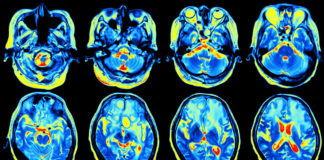

Functional MRI used to investigate new drugs for drug relapse prevention

Researchers in the UK are studying the effects of experimental medicines using functional MRI (fMRI) technology to investigate the neuropharmacology of brain processes including...